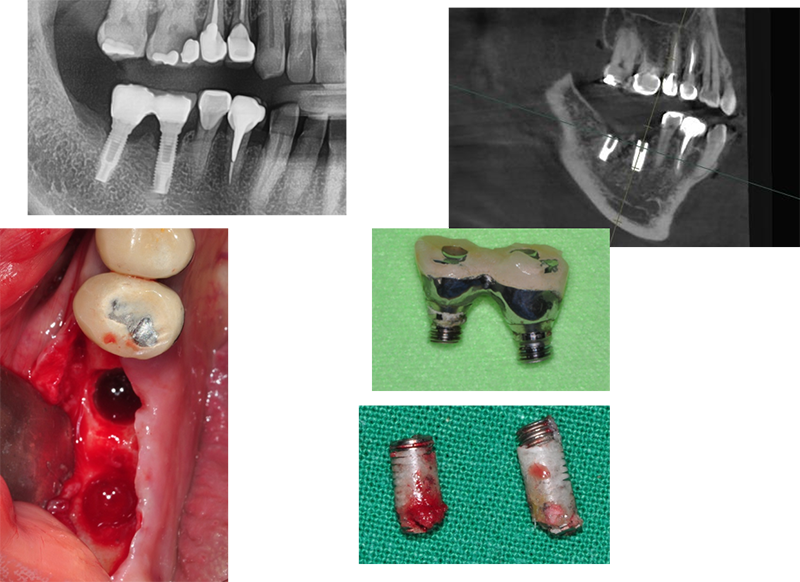

Bone loss

에 따른 픽스쳐 파절

Ext. type 3.75mm 직경의 임플란트.

Bruxism 이 있는 환자로써 심고 기능한 지 15년 만에 부러져서 내원했다.

직경이 3.75mm로 예전 regular에 해당하지만 4.0mm보다 부러지는 경우가 많다.

또한 Ext은 보철이 올라가면 플랫폼에서 1.5mm 골흡수가 거의 필연적으로 일어난다. 이번 경우도 골흡수와 깊은 연관이 있다고 여겨진다.

앞에서 얘기한 것처럼 제일 중요한 것은 “변 연골 흡수”가 일어나지 말아야 한다.

Submerged implant의 단점

Wide fixture(직경 5.5mm)

Sub type은 픽스쳐 직경과는 별 개로 어벗은 모두 동일한 사이즈다. 특징이자 장점이다. 픽스쳐가 부러지지 않아서 다행이다. 그러나 어벗의 밑동이 부러진 것도 매우 큰 합병증이다. 부러진 밑동을 깨끗하게 빼내는 것도 상당히 힘든 일이다.